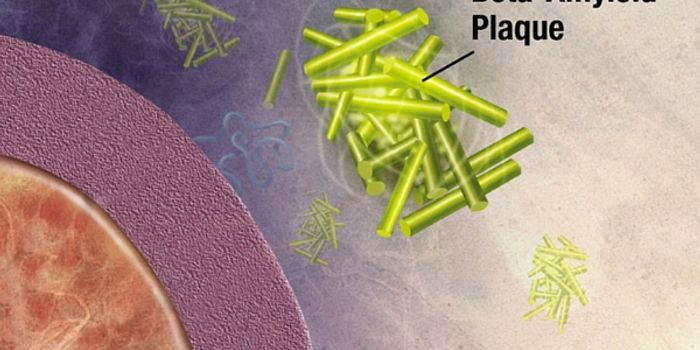

JUN 08, 2016NeuroscienceIt’s been known for a while that plaques of the protein amyloid beta are part of the pathology of Alzheimer’ ...

MAY 11, 2016ImmunologyThe brain’s immune system potentially could be harnessed to help clear amyloid plaques, which are a hallmark of Al ...

APR 05, 2016NeuroscienceAlzheimer’s Disease (AD) is the most common form of dementia, currently affecting 5.5 million people in the U.S. T ...

SEP 27, 2015NeuroscienceAmyloids, fibrous protein clumps often associated with diseases such as Alzheimer’s disease, form characteristic p ...